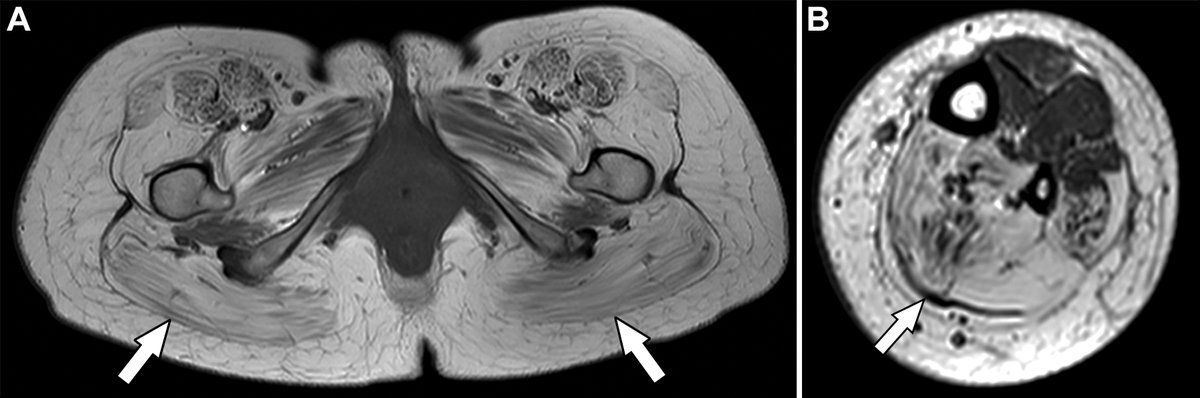

Myopathies are heterogeneous disorders affecting the structure & metabolism of skeletal muscles. At imaging, radiologists can identify specific characteristics that correlate with clinical and genetic findings to differentiate among entities. https://t.co/8HKU2wIPBg